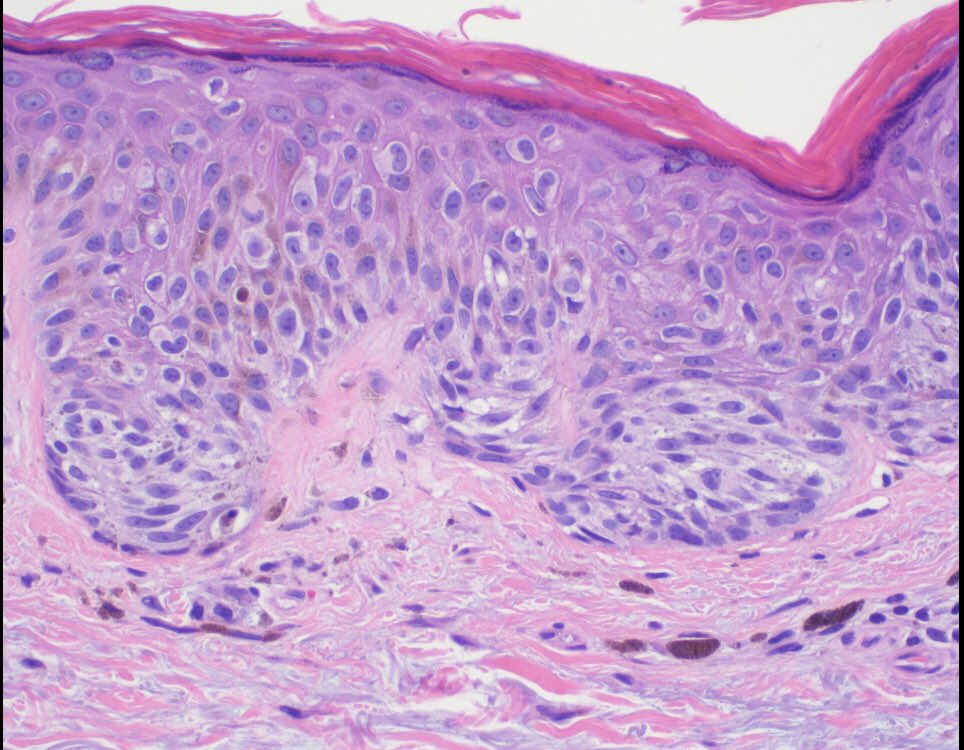

It seems like a banal SCC with keratoacanthomatous features, but it is a drug reaction pattern to treatment for metastatic melanoma with BRAF inhibitor. Take care

#dermatology#oncology#dermpath#dermatopathology#patologia#patología#pathologypic.twitter.com/ayrciZL6cL